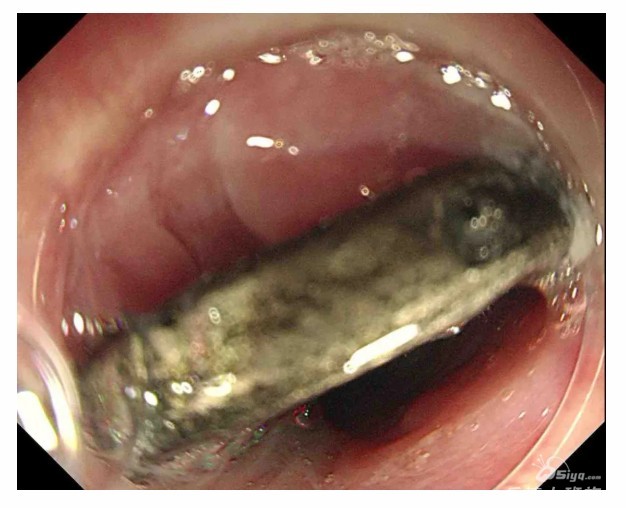

一枚一元硬币,竟在 4 岁宝宝的食管里 “潜伏” 了两个多月,直到孩子喊胸口不适,家人才惊觉异常,这场意外也让一家人捏了一把冷汗。幸运的是,乐清市第二人民医院内镜科 + 麻醉科多学科联手,精准操作下仅用两分钟 ...